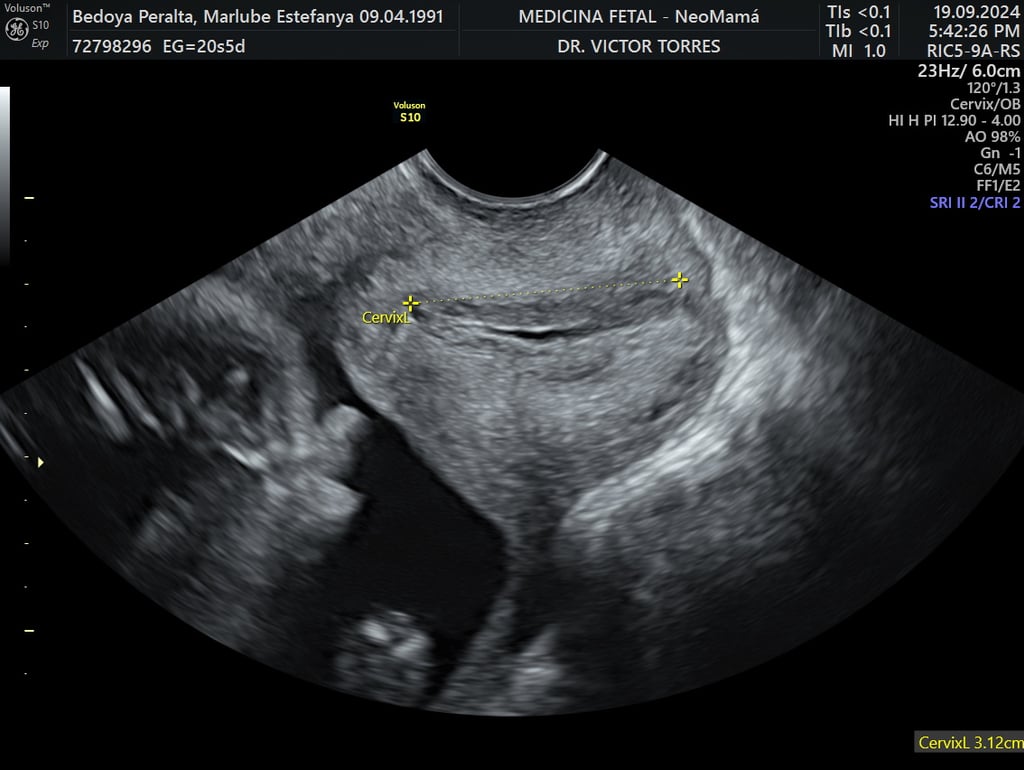

cervicometría